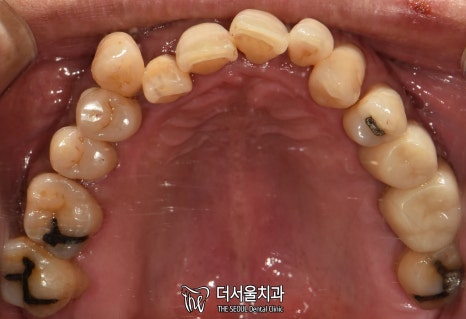

교합면을 확인했을 때도 마찬가집니다.

인접면에 있는 충치와

누워있는 사랑니까지 찾아볼 수 있었습니다.

단기간 내에 끝낼 수 없는 케이스죠.